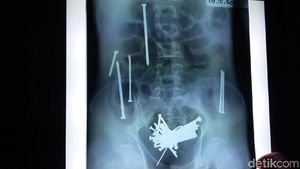

Ini Paku-paku yang Dimakan Wawan hingga Akhirnya Tewas